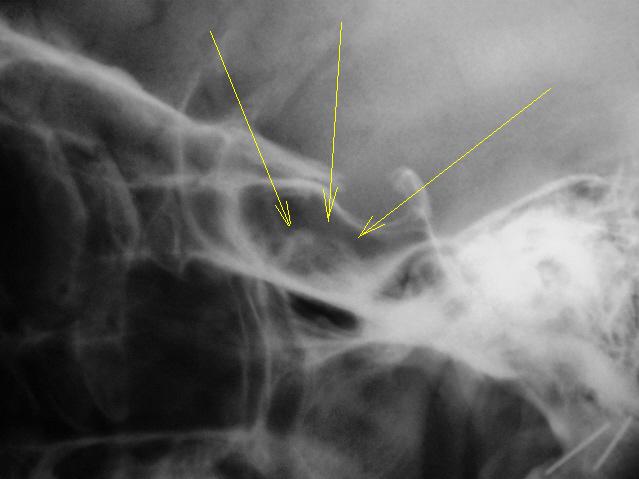

Как следует расценить "тень" на фоне клиновидной (основной) пазухи.

А  где прямая  проекция. Может это  сфеноидит.

Наверное, сфеноидит. Похоже, что клиновидная пазуха разделена сагиттальной костной перегородкой на две неравные части. Пневматизация бОльшей правой половины не нарушена. А левой - снижена. Вероятно, эта левая часть пазухи и дает неравномерное снижение пневматизации на боковой рентгенограмме. В любом случае, если у пациента головные боли, то вероятность сфеноидита ещё выше (неврологи, кстати, не всегда вспоминают про сфеноидит, когда пользуют пациентов с головной болью). А чтобы сфеноидит доказать без КТ, надо снять околоносовые пазухи с открытым ртом (извините за банальные рекомендации).